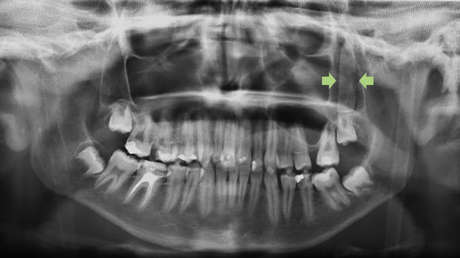

En el Hospital Universitario Virgen del Rocío le hicieron una radiografía y una tomografía computarizada que reveló la existencia detrás de un pómulo de un objeto rectangular de unos 3,5 centímetros de longitud "que tenía forma de hoja de cuchillo".

"Es un caso relativamente raro", reza el estudio, que recuerda que esta parte del cuerpo se encuentra bien protegida por el pómulo. Los médicos le practicaron una cirugía para extraer el objeto de cristal a través de la boca del chico desde la parte inferior de la mejilla. Tras la intervención quirúrgica, el joven pudo mover de nuevo la mandíbula con normalidad y no tuvo complicaciones en los siguientes seis meses.